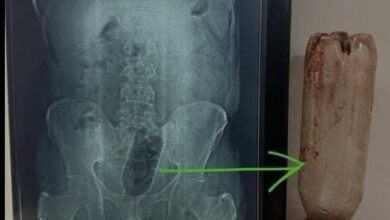

पुलिस जांच में जो तस्वीर सामने आई, उसने हर किसी को सन्न कर दिया। जिस व्यक्ति ने बच्ची के परिजनों के साथ उसे ढूंढने का नाटक किया, वही अब इस जघन्य हत्याकांड का मुख्य संदिग्ध बनकर उभरा है। सूत्रों के मुताबिक, 25 फरवरी की देर रात बच्ची का शव किरायेदार के कमरे से आटे के ड्रम में छिपाकर रखा हुआ मिला। इस खुलासे के बाद पूरे इलाके में चीख-पुकार मच गई। परिवार जो अब तक उम्मीद कर रहा था कि बच्ची कहीं से जिंदा मिल जाएगी, उसके सामने जब यह भयावह सच आया, तो जैसे सब कुछ थम गया।

पोस्टमार्टम रिपोर्ट ने इस हत्याकांड को और भी भयावह बना दिया। रिपोर्ट के मुताबिक, मासूम की गला काटकर हत्या की गई। इतना ही नहीं, उसके शरीर पर कई चोटों के निशान भी मिले हैं, जो यह संकेत देते हैं कि बच्ची ने शायद आखिरी वक्त तक संघर्ष किया होगा। पुलिस ने स्लाइड सुरक्षित रखी है, जिसे जांच के लिए भेजा जाएगा। इससे यह साफ है कि पुलिस हत्या के पीछे की असली वजह तक पहुंचने के लिए हर वैज्ञानिक और फोरेंसिक पहलू को खंगाल रही है। फिलहाल पुलिस इस बात की जांच कर रही है कि हत्या के पीछे गलत नीयत, व्यक्तिगत रंजिश, या किराए के विवाद में से कौन सा कारण ज्यादा मजबूत है।